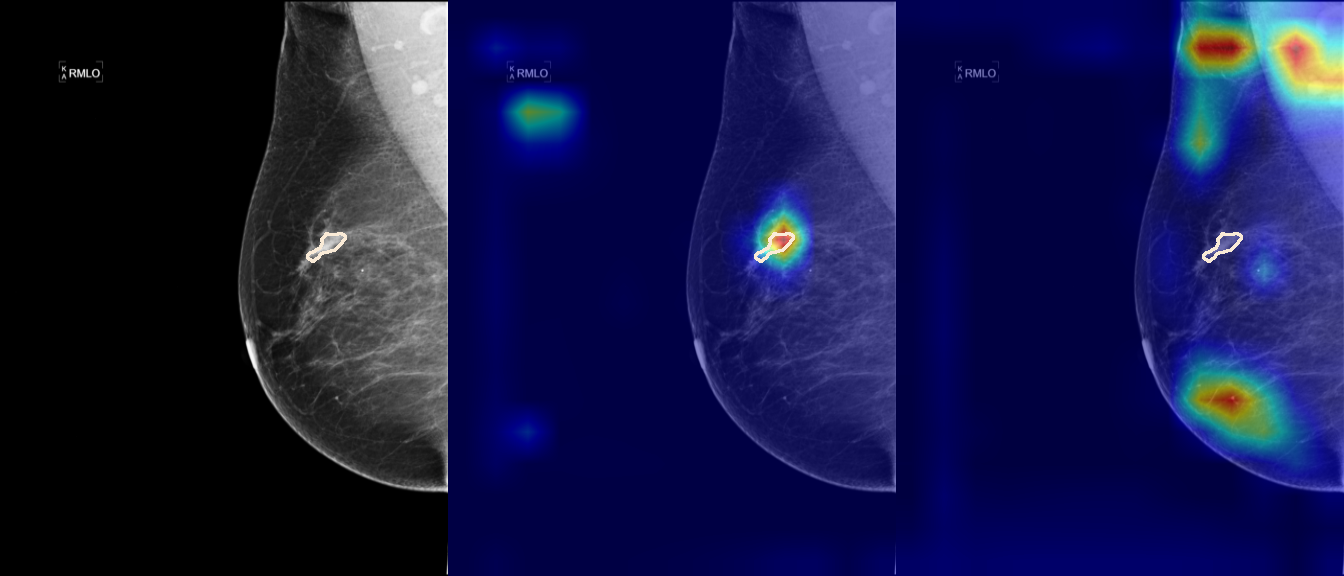

To interpret the decision-making process behind the quantitative results, we visualized Class Activation Maps (CAM) for the top-performing methods, ERM and VREx. Figures 1 through 2 illustrate discriminative regions identified by the models within the full mammograms.

Localization of Clinical Features: A key concern in medical AI is whether high performance stems from genuine pathology detection or spurious background correlations. Our visualizations suggest that Standard ERM achieves its superior quantitative performance by predominantly prioritizing clinical cues. As shown in the top rows of the Figure 1 and Figure 2, the ERM-trained models consistently focus attention on the specific lesion regions within the breast tissue. This demonstrates that despite lacking explicit invariance constraints, ERM is capable of learning robust, medically relevant features when trained on diverse multi-source data.

Attention Drift in Both Methods: While both ERM and VREx generally identify the correct region of interest in successful cases, neither method is immune to attention drift. We observe instances in both training paradigms where the model focuses on irrelevant areas, such as healthy fibroglandular tissue or background artifacts (e.g., rows 5 and 6 in Figure 1). This indicates that while VREx is designed to penalize instability, it does not guarantee perfect anatomical focus compared to the unconstrained ERM baseline.